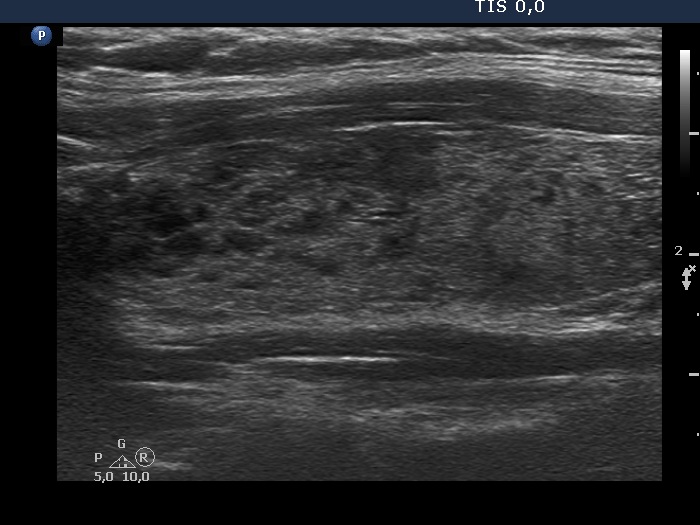

Discrete lesion or nodule in Hashimoto's thyroiditis - case 27 (1029) (ultrasonographic picture 6)

Left lobe, longitudinal view. The echogenicity index in this section is around 50%. None of the discrete hypoechogenic areas corresponds to a nodule.